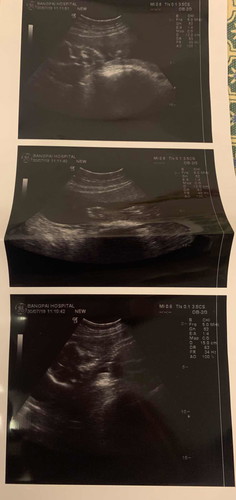

อยากคอนเฟริมผลอัลตร้าซาวน์หน่อยคะ

อยากคอนเฟริมผลอัลตร้าซาวน์หน่อยคะ พอดีตอนซาวหมอโดนเร่งให้ไปห้องคลอดต่อ เราได้เห็นจอแปปเดียวเองคะ ไม่มีเวลาได้คุยกับหมอเลย แต่หมอบอกว่า ผู้ชาย 80% กว่าจะได้เจอหมอซาวอีกทีก็ตอนแปดเดือนเลย แม่ๆคนไหนพอดูออกไหมคะ ว่าเพศอยู่ตรงไหน แล้วเป็นผู้ชายจริงไหมคะ